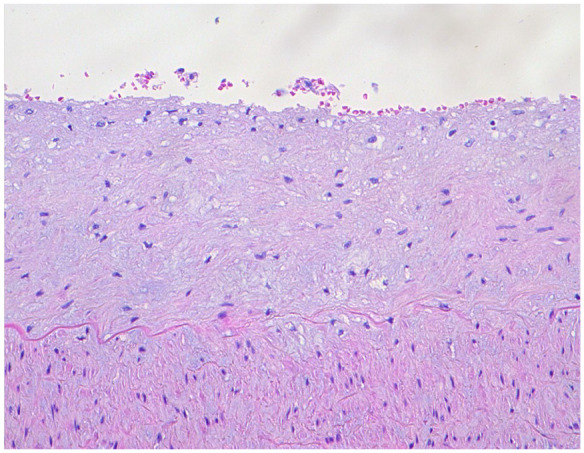

Atherosclerosis is a complex disease characterized by the accumulation of plaques in arterial walls. Understanding its pathogenesis remains incomplete, with factors like inflammation, oxidative stress, and hypertension playing critical roles. The disease exhibits preferential localization of plaques, with variability observed even within the same individual. Genetic, environmental, and lifestyle factors contribute to its heterogeneity. Histological plaque phenotypes vary widely, prompting classification schemes focusing on systemic and local factors deteriorating fibrous caps. Recent research highlights differences in plaque histology among arterial systems, suggesting unique pathophysiological mechanisms. This study reports on multiple atherosclerotic plaques detected at autopsy in various vascular sites of a single subject, emphasizing their histological diversity and underscoring the systemic nature of atherosclerosis.

Abstract Image